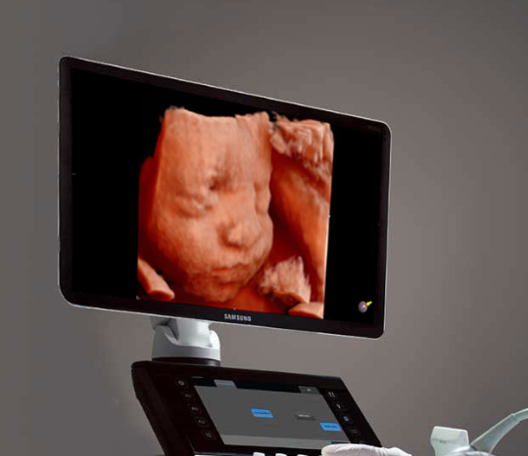

Providing comprehensive prenatal imaging to monitor the development and health of your baby, ensuring both mother and child receive exceptional care.

At Dr. Nagare Diagnostics, we provide high-quality anomaly scans to detect any abnormalities in the fetus, ensuring the health and well-being of the mother and baby. Our state-of-the-art imaging center offers advanced technology and experienced professionals to perform these crucial diagnostic procedures.